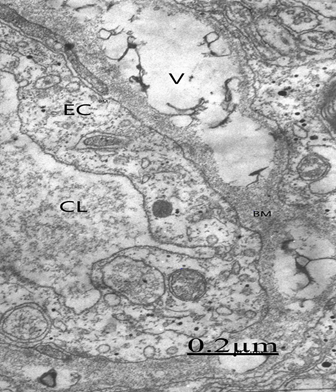

The cortical capillaries exhibit increased vesicular and vacuolar trasnendothelial transport (Figure 1).7,8 In addition we found closed and open endothelial junctions (Figure 2).9,10 Some cortical capillaries show in severely edematous areas the formation of transendothelial channels.11 Cortical capillary showing deep invaginations of peripheral endothelial cytoplasmic zone (PEZ) extending to the vicinity of basement membrane (BM) (long arrows) and closed interendothelial junction (short arrows), suggesting parajunctional transitory transendothelial channel formations to increase transfer of proteinaceous edema fluid from capillary lumen toward the brain parenchyma as a pathogenetic mechanism of vasogenic brain edema. Thickening and vacuolization of basement membrane, and glio-basal dissociation, and proliferation of connective fibers are observed after repeated ischemic and hypoxic processes (Figure 3).12,13 The pericites embedded into the basement membrane show shuttle micropinocitotic vesicles indicating their participation on transcapillary transport (Figure 4).14,15

Figure 1 Brain trauma. Subdural hematoma. Cortical capillary showing increased vacuolar transport (V) at the endothelial cell peripheral cytoplasm (EC), suggesting the genesis of vasogenic brain edema. Note the thickening basement membrane (BM) and the embedded pericite (P). The capillary lumen (CL) exhibits the plasma serum proteinaceous granular substance.